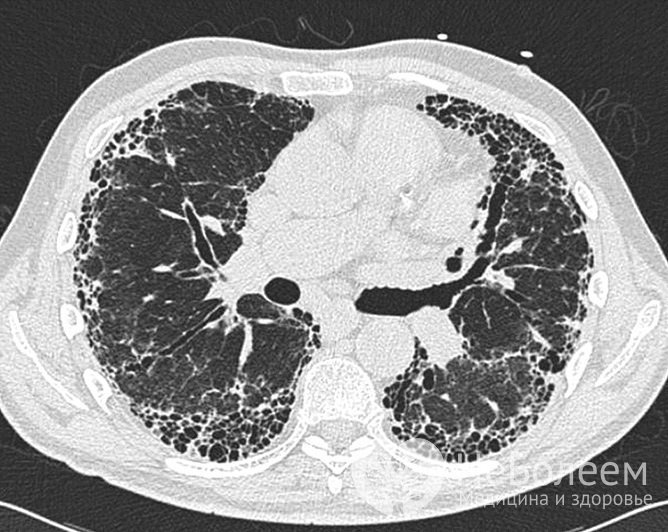

Клинический анализ крови имеет важное диагностическое значениеНа рентгенограмме грудной клетки определяется диффузное двустороннее затемнение легочных полей или прогрессирующие диффузные изменения по типу матового стекла и консолидация. На снимках видно диффузное поражение, определяется утолщение бронхиальной стенки, очаговые или диффузные изменения по типу матового стекла или линейное усиление легочного рисунка. Позже появляются бронхоэктазы (необратимые расширения участков бронха).

При выраженном фиброзе определяется уменьшение объема преимущественно нижних долей легких.

Диагноз подтверждается с помощью компьютерной томографии высокого разрешения, которая помогает оценить распространенность патологического поражения легочной ткани, стадию, активность и темпы прогрессирования фиброзного процесса.